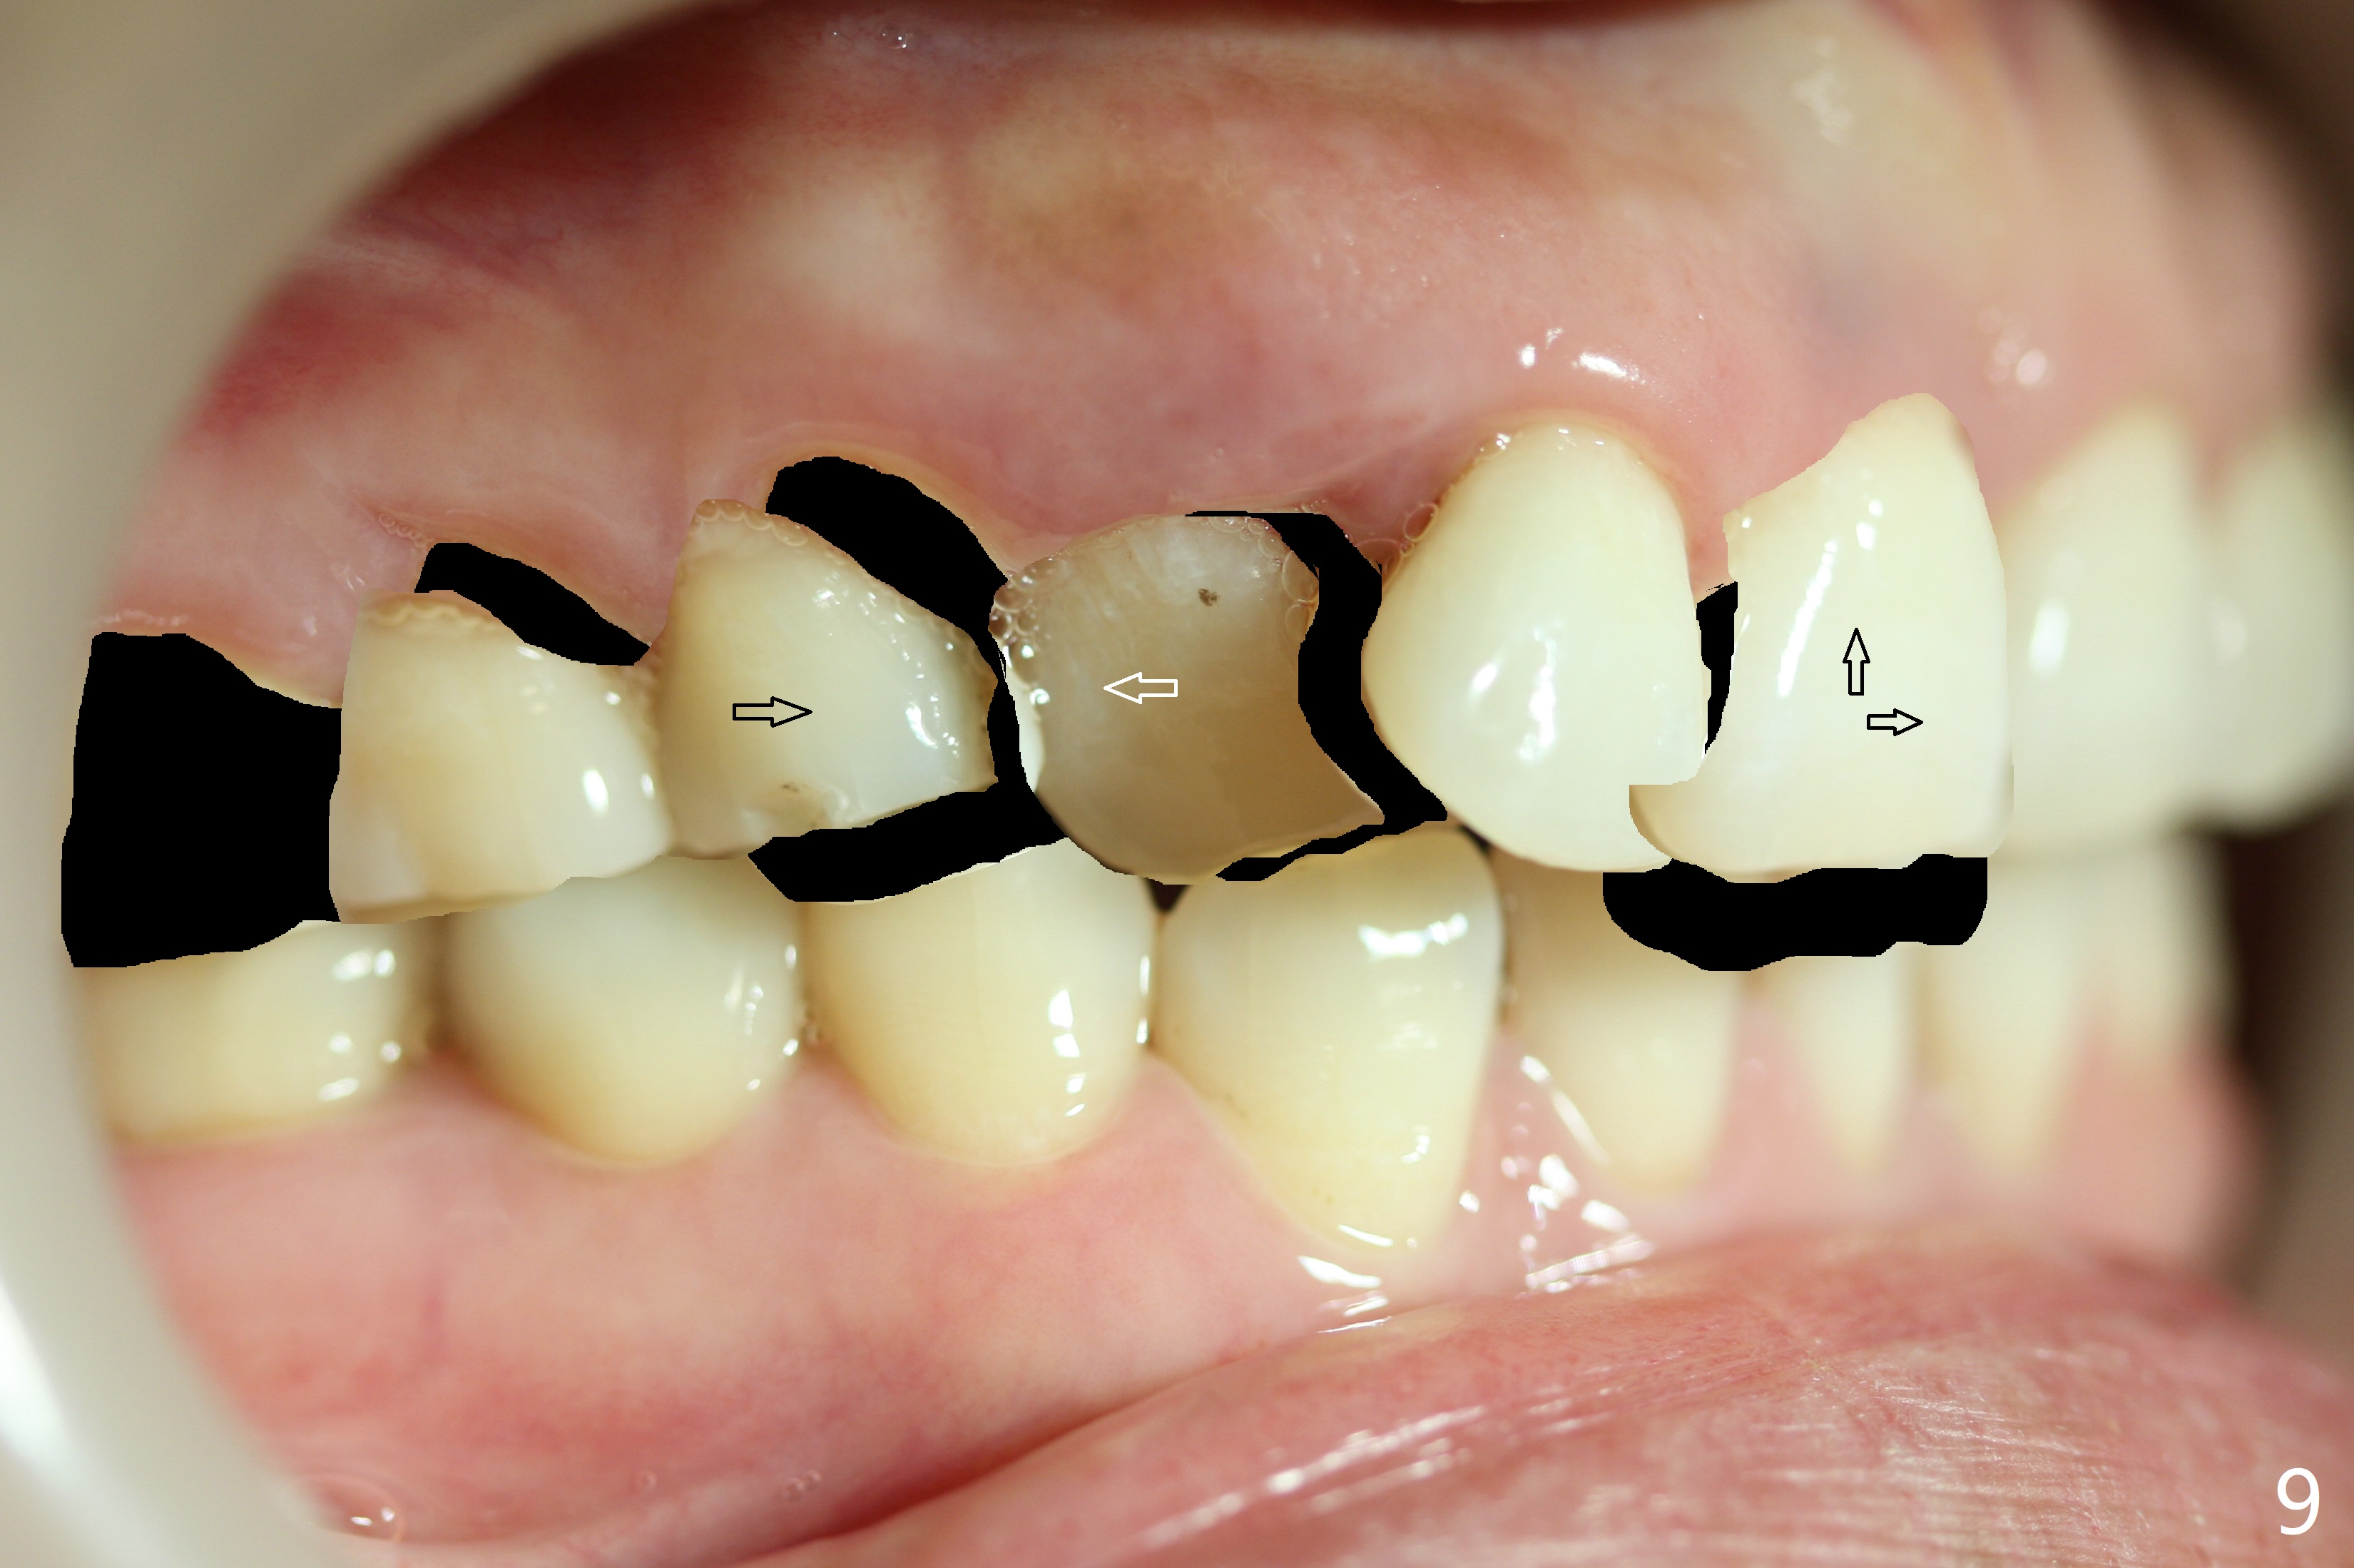

In addition, the upper dental midline deviates (Fig.2). It appears necessary to extract U4s (Fig.6,8: X) for realignment (Fig.9,11). When UR1 is intruded orthodontically (compare Fig.6,7 with 9) without increased mobility, it will be retained with lingual retainer. Otherwise it will be extracted for implant. Model surgery confirms the necessity of U4 extraction.